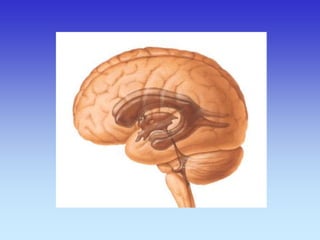

Sagitalni presjek